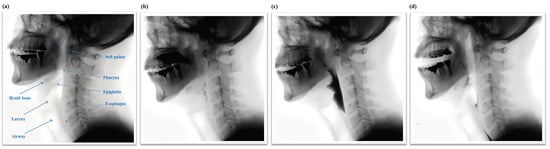

The swallowing process is subdivided into three phases, the oral phase, the pharyngeal phase, and the esophageal phase, as shown in Figure 1. Swallowing is a rapid and complex function involving the coordinated contraction or inhibition of musculature in the mouth, tongue, larynx, pharynx, and esophagus [,]. In the oral phase, food is chewed and mixed with the saliva to form a bolus. The tongue pushes the bolus from anterior to posterior of the oral cavity via squeezing motion. Then, in the pharyngeal phase, the bolus is propelled from the oral cavity to the pharynx as the soft palate elevates and presses against the posterior wall of the pharynx. At this point, the hyoid bone and the larynx elevate and the epiglottis folds downward to protect the airway. This critical step makes the pharyngeal phase a crucial stage of swallowing as it prevents the transport of the bolus to the airway system. After the airway is protected, the tail of the bolus exits though opening of the upper esophageal sphincter. Finally, in the esophageal phase, the bolus passes down the esophagus to the stomach.

Figure 1.

(a) Structural anatomy and normal physiologic swallowing of a thick liquid bolus in (b) the oral phase; (c) the pharyngeal phase; and (d) the esophageal phase.